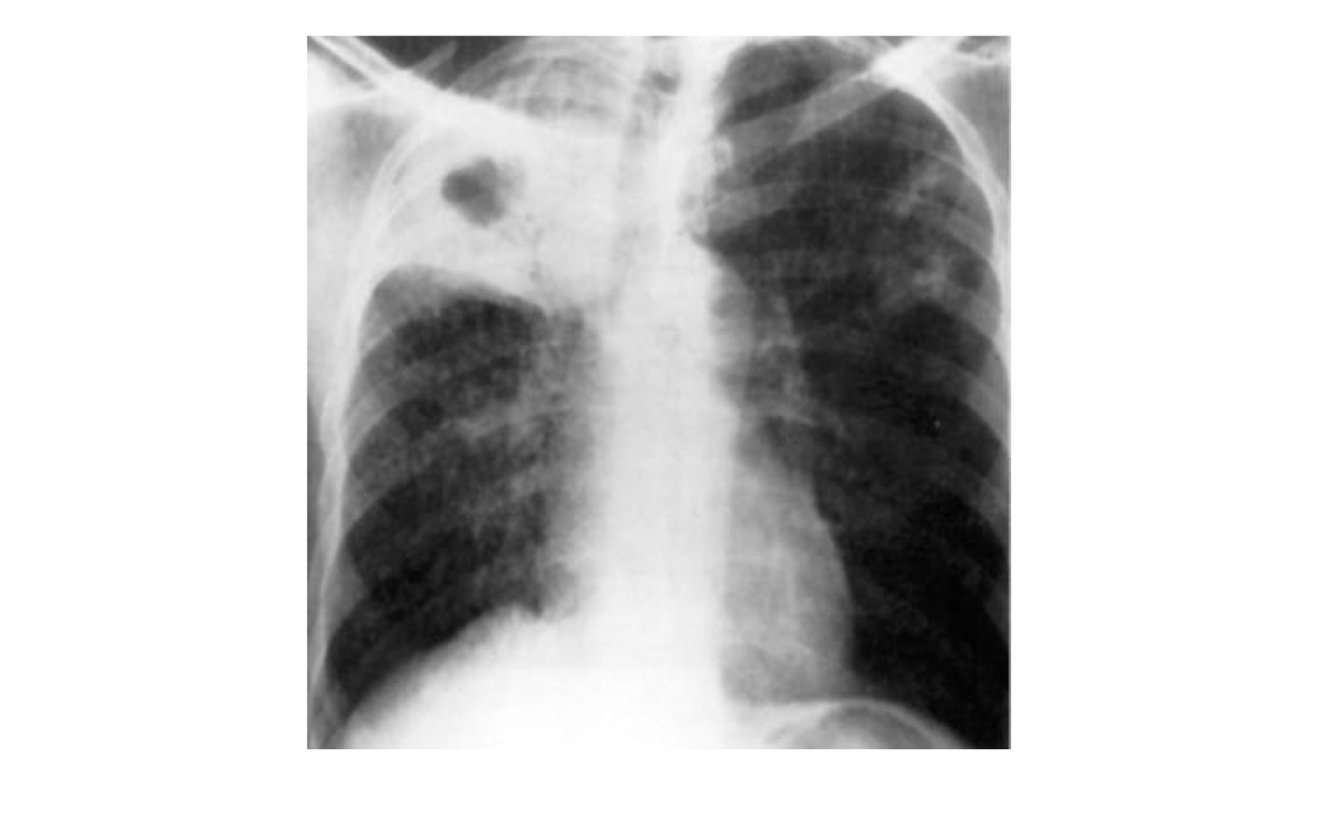

Qual a forma de TB demonstrada nesse exame?

TB cavitária